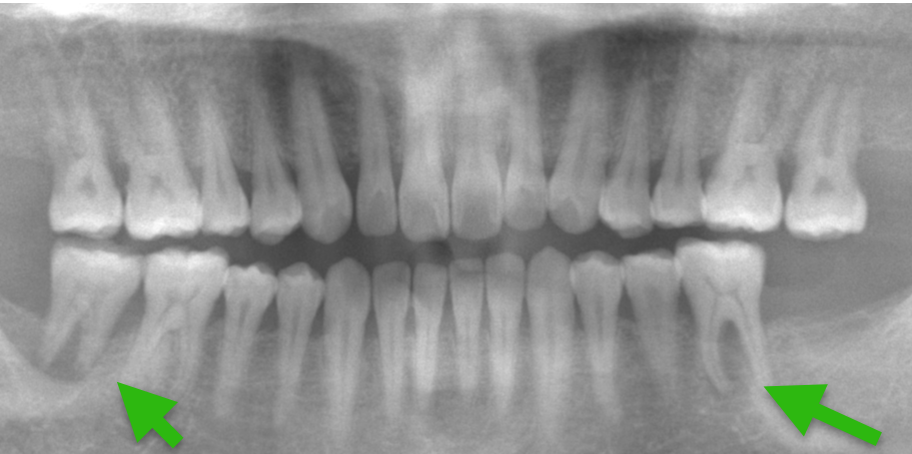

Case3.

| 主 訴 | 歯がない部分を治療したい |

| 治療期間 | 約6ヶ月 |

| 治療費 | 合計3,278,000円(税込) |

| 治療内容 | 治療1回目 保存不可能な歯の抜歯 治療2回目 CT撮影にて顎の骨にインプラントが入ることを確認し、サージカルガイドの型取り 治療3回目 インプラントを入れる治療 治療4回目 縫合してある糸をとり、周りをクリーニング 治療5回目 インプラントに土台を立てる治療 治療6回目 上部構造(被せ物)の型取り 治療7回目 上部構造(被せ物)をセット |

| 治療のリスク | インプラントの手術の後は腫れ、 痛みが出ることがあり ます。 |